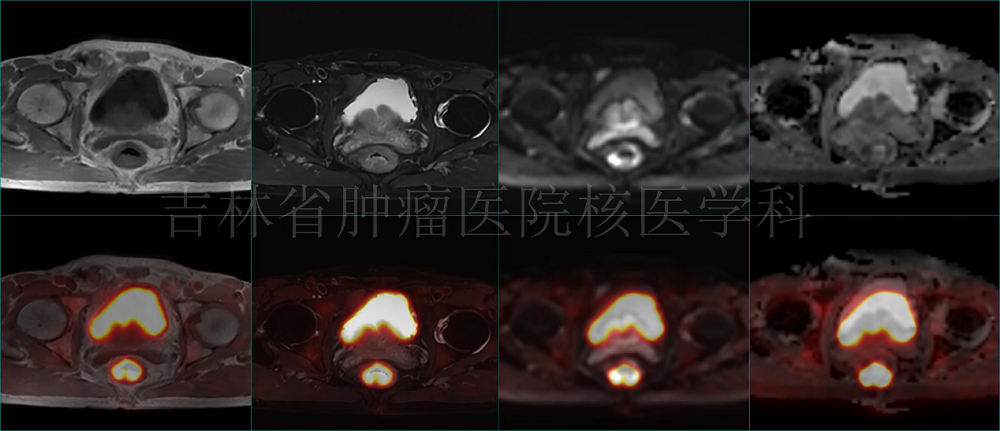

病例2 PET/MR直肠癌治疗前分期:直肠癌T2N0M0